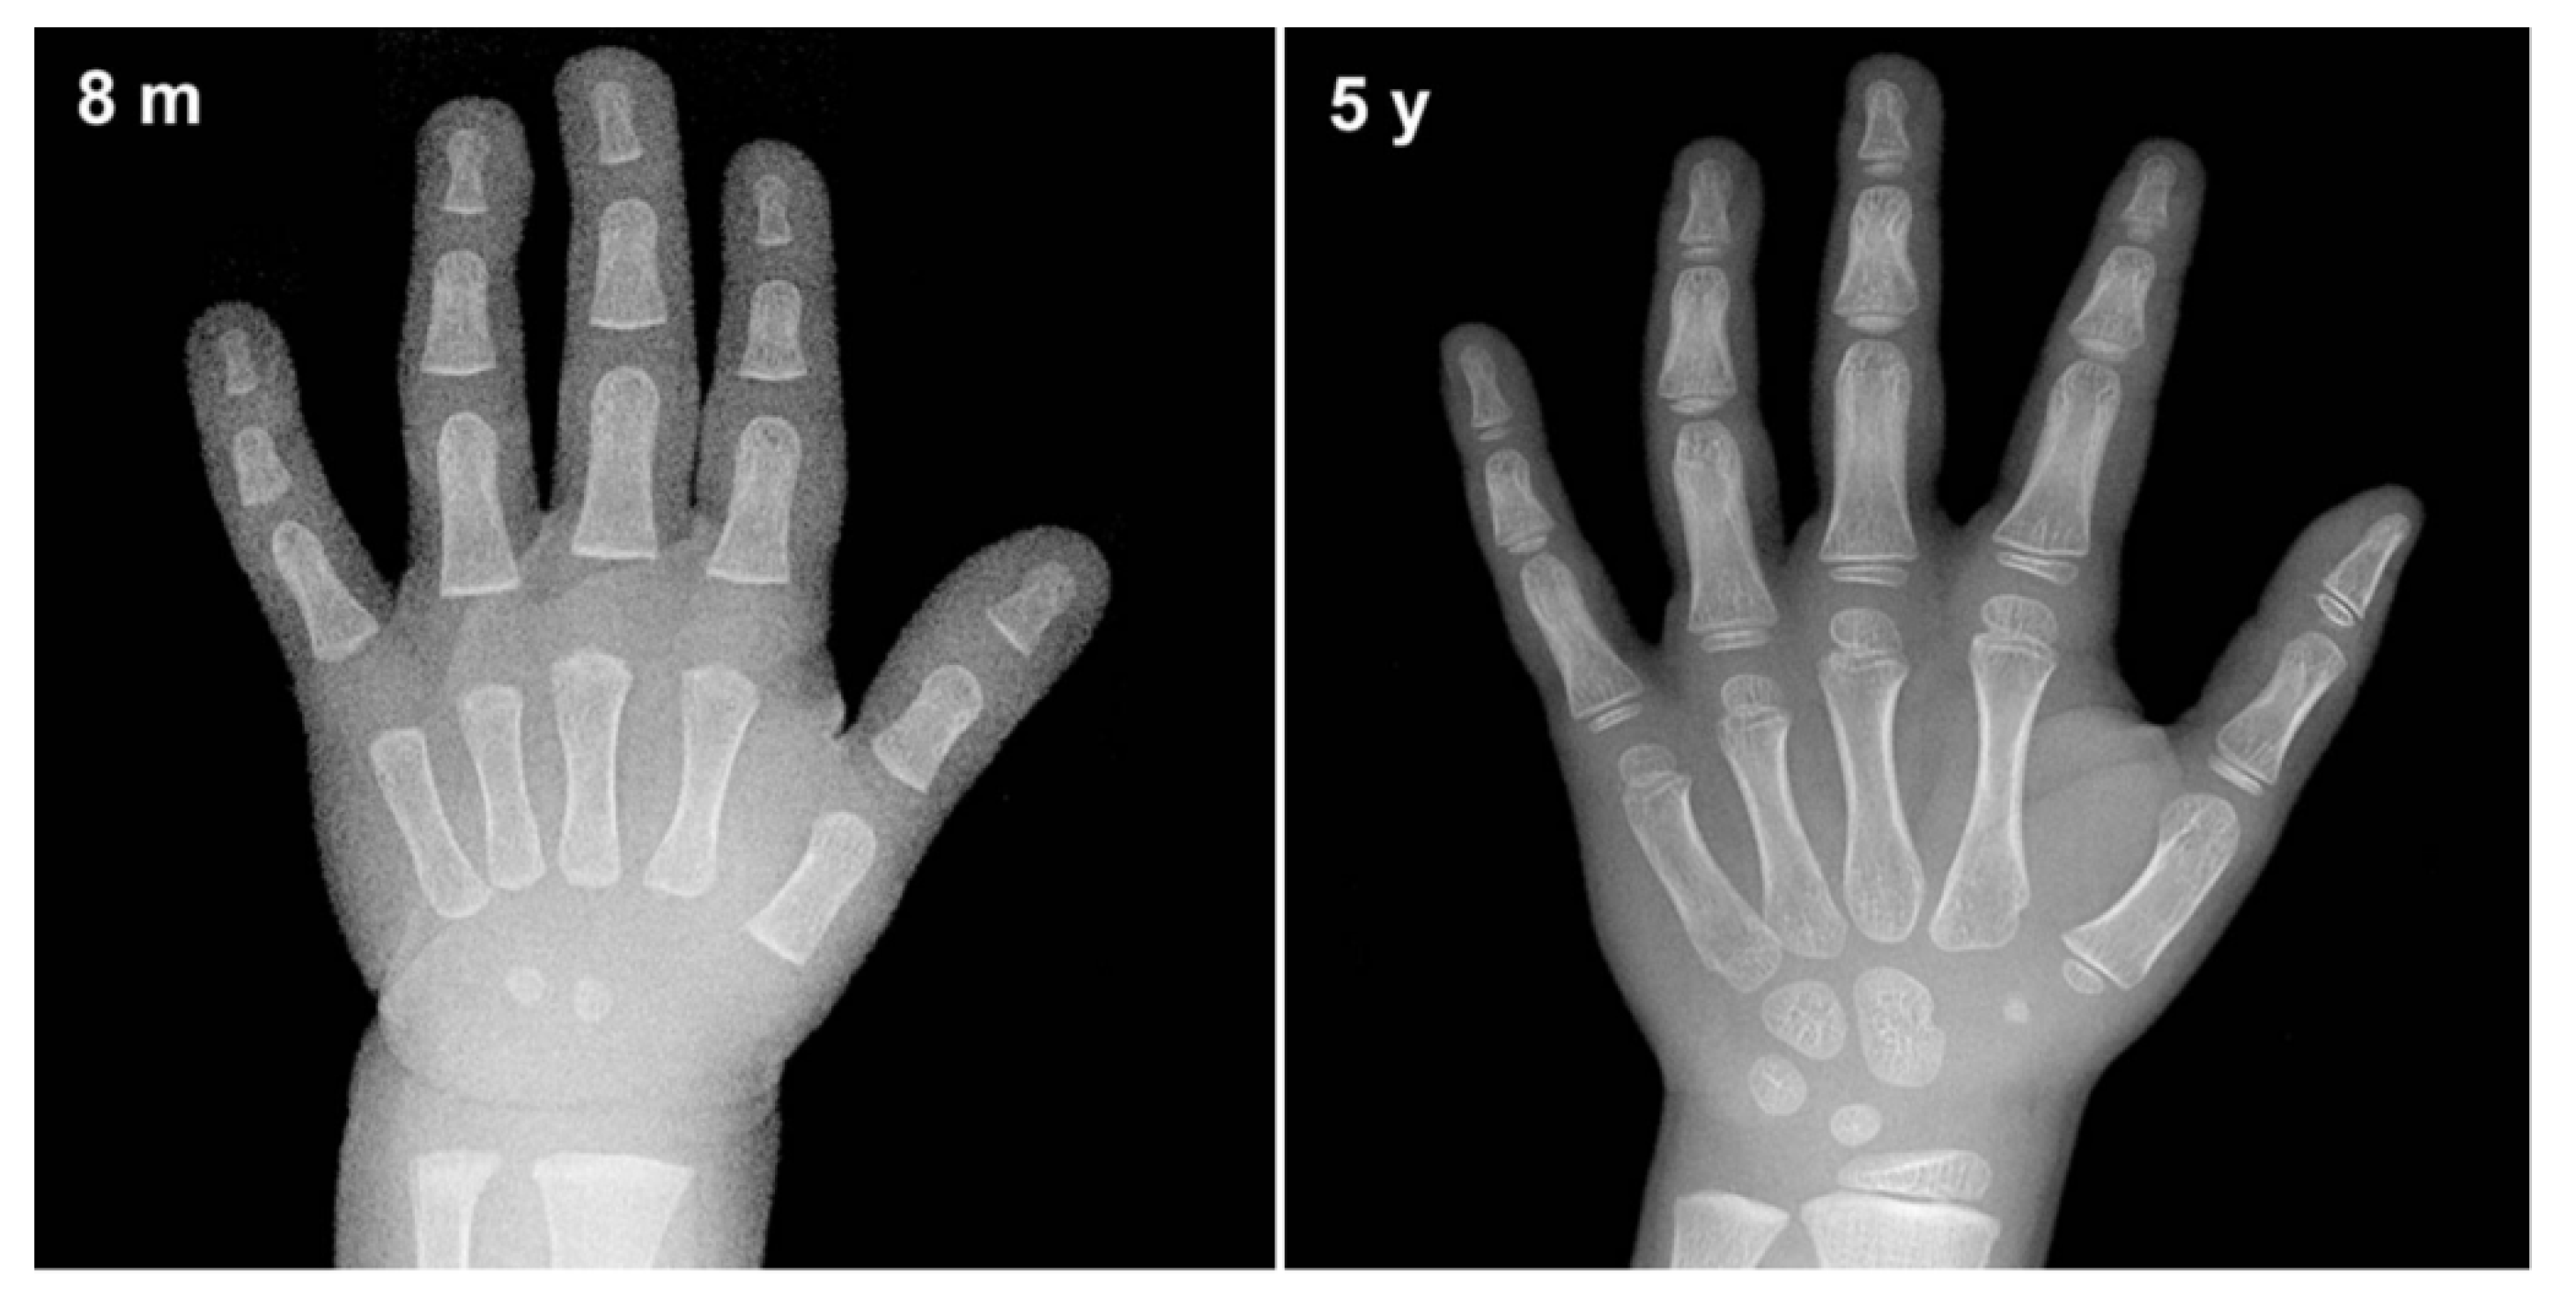

From utahpedsrad.blogspot.com

Utah Pediatric Radiology Bone age determination in infants Bone Age Test Results Bone age represents a common index utilized in pediatric radiology and endocrinology departments worldwide for the. Describe the indications for determining. A bone age study helps doctors estimate the maturity of a child's skeletal system. Performing bone age assessments can assist clinicians in diagnosing central precocious puberty. Bone age continues to be a valuable tool in assessing children’s health. New. Bone Age Test Results.